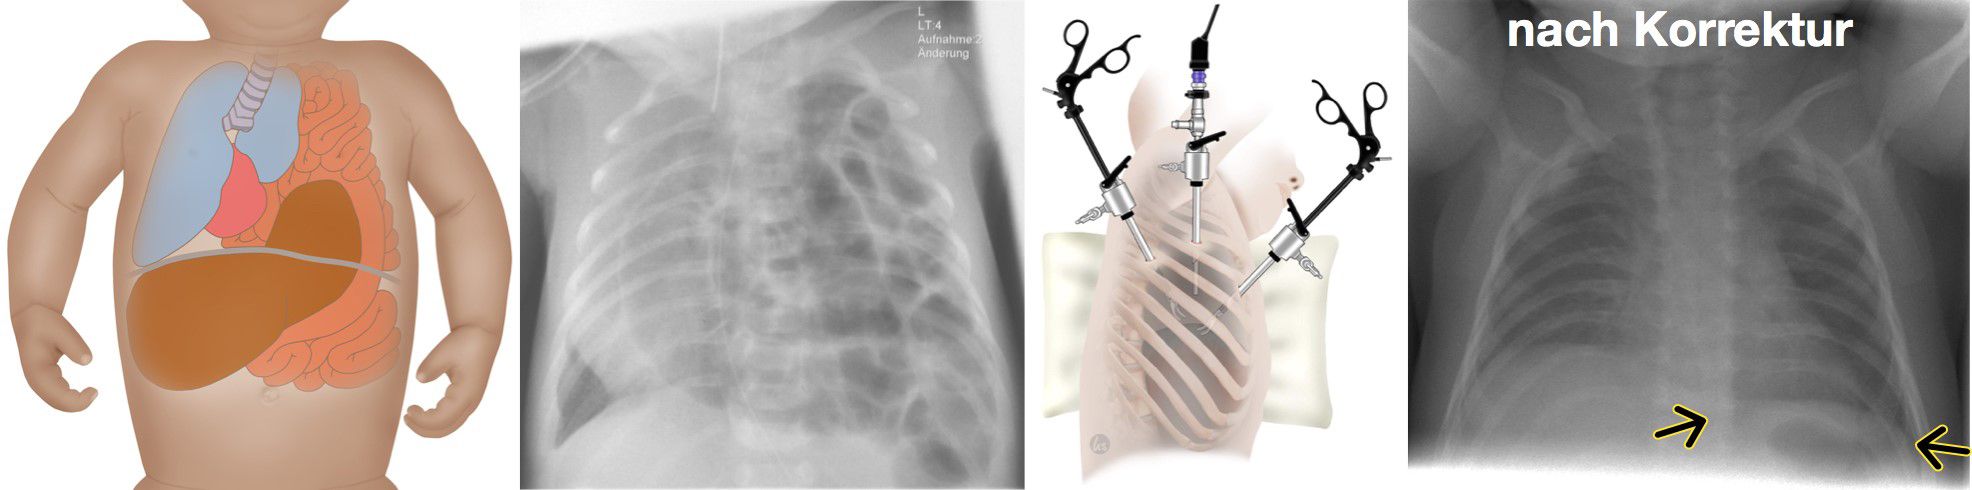

Zwerchfellhernien sind angeborene Defekte des Zwerchfells. Diese werden bei den meisten Kindern vor Geburt im Ultraschall erkannt. Je nach Lokalisation und Ausprägung verursachen sie teilweise erhebliche Probleme mit der Atmung für das Neugeborene. Deshalb sollten alle Schwangeren bei deren Kindern diese Fehlbildung festgestellt wird eng an ein Zentrum wie Tübingen angebunden werden und das Kind dort zur Welt bringen. bereits vor Geburt  Bereits in der Diagnostik vor Geburt mit Ultraschall und Kernspintomographie lässt sich das Risiko für die Beeinträchtigung der Atmung anhand der Lungengröße abschätzen. Damit ist gewährleistet, dass die Geburtshelfer, die Neonatologen und Kinderintensivmediziner darauf vorbereitet sind und alle Therapiemöglichkeiten direkt zur Verfügung stehen. Dies umfasst am Universitätsklinikum Tübingen alle modernen Therapieoptionen beginnend von Eingriffen im Mutterleib, über eine direkte Versorgung des Neugeborenen solange es noch durch die Nabelschnur versorgt wird bis hin zu speziellen Beatmungsformen nach Geburt und der Sauerstoffzufuhr über das Blut (ECMO). Als überregionales Zentrum für Fehlbildungen beim Neugeborenen sind alle diese Therapieformen bei uns mit jahrelanger Erfahrung etabliert.

Nach Geburt wird das Kind zunächst über mehrere Tage hinweg intensivmedizinisch stabilisiert, bis eine Operation möglich ist. Nach entsprechender Patientenselektion wird die Korrektur minimalinvasiv oder offen chirurgisch durchgeführt.

Zwerchfellhernie: Abb. links nach Korrektur.

Zwerchfellhernie: Abb. rechts nach Korrektur.